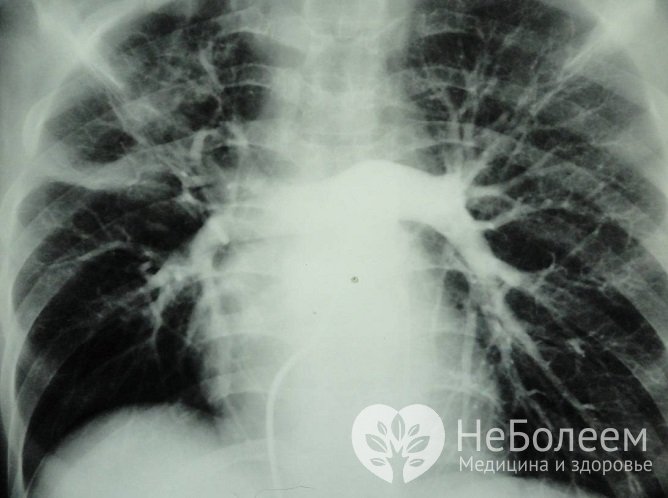

Существует несколько методов, которые применяются в клинике для измерения уровня давления в правых отделах сердца. Главные – инвазивный метод катетеризации сердца и неинвазивная эхокардиография. Катетеризация обеспечивает наиболее точный результат, но используется реже по причине связанных с ней рисков. Также проводится рентгенография органов грудной клетки, ЭКГ, спирометрия (дыхательные пробы).

Один из методов диагностики ЛГ – рентгенография грудной клеткиБиохимический анализ крови может указать на патологию со стороны сердечной мышцы.